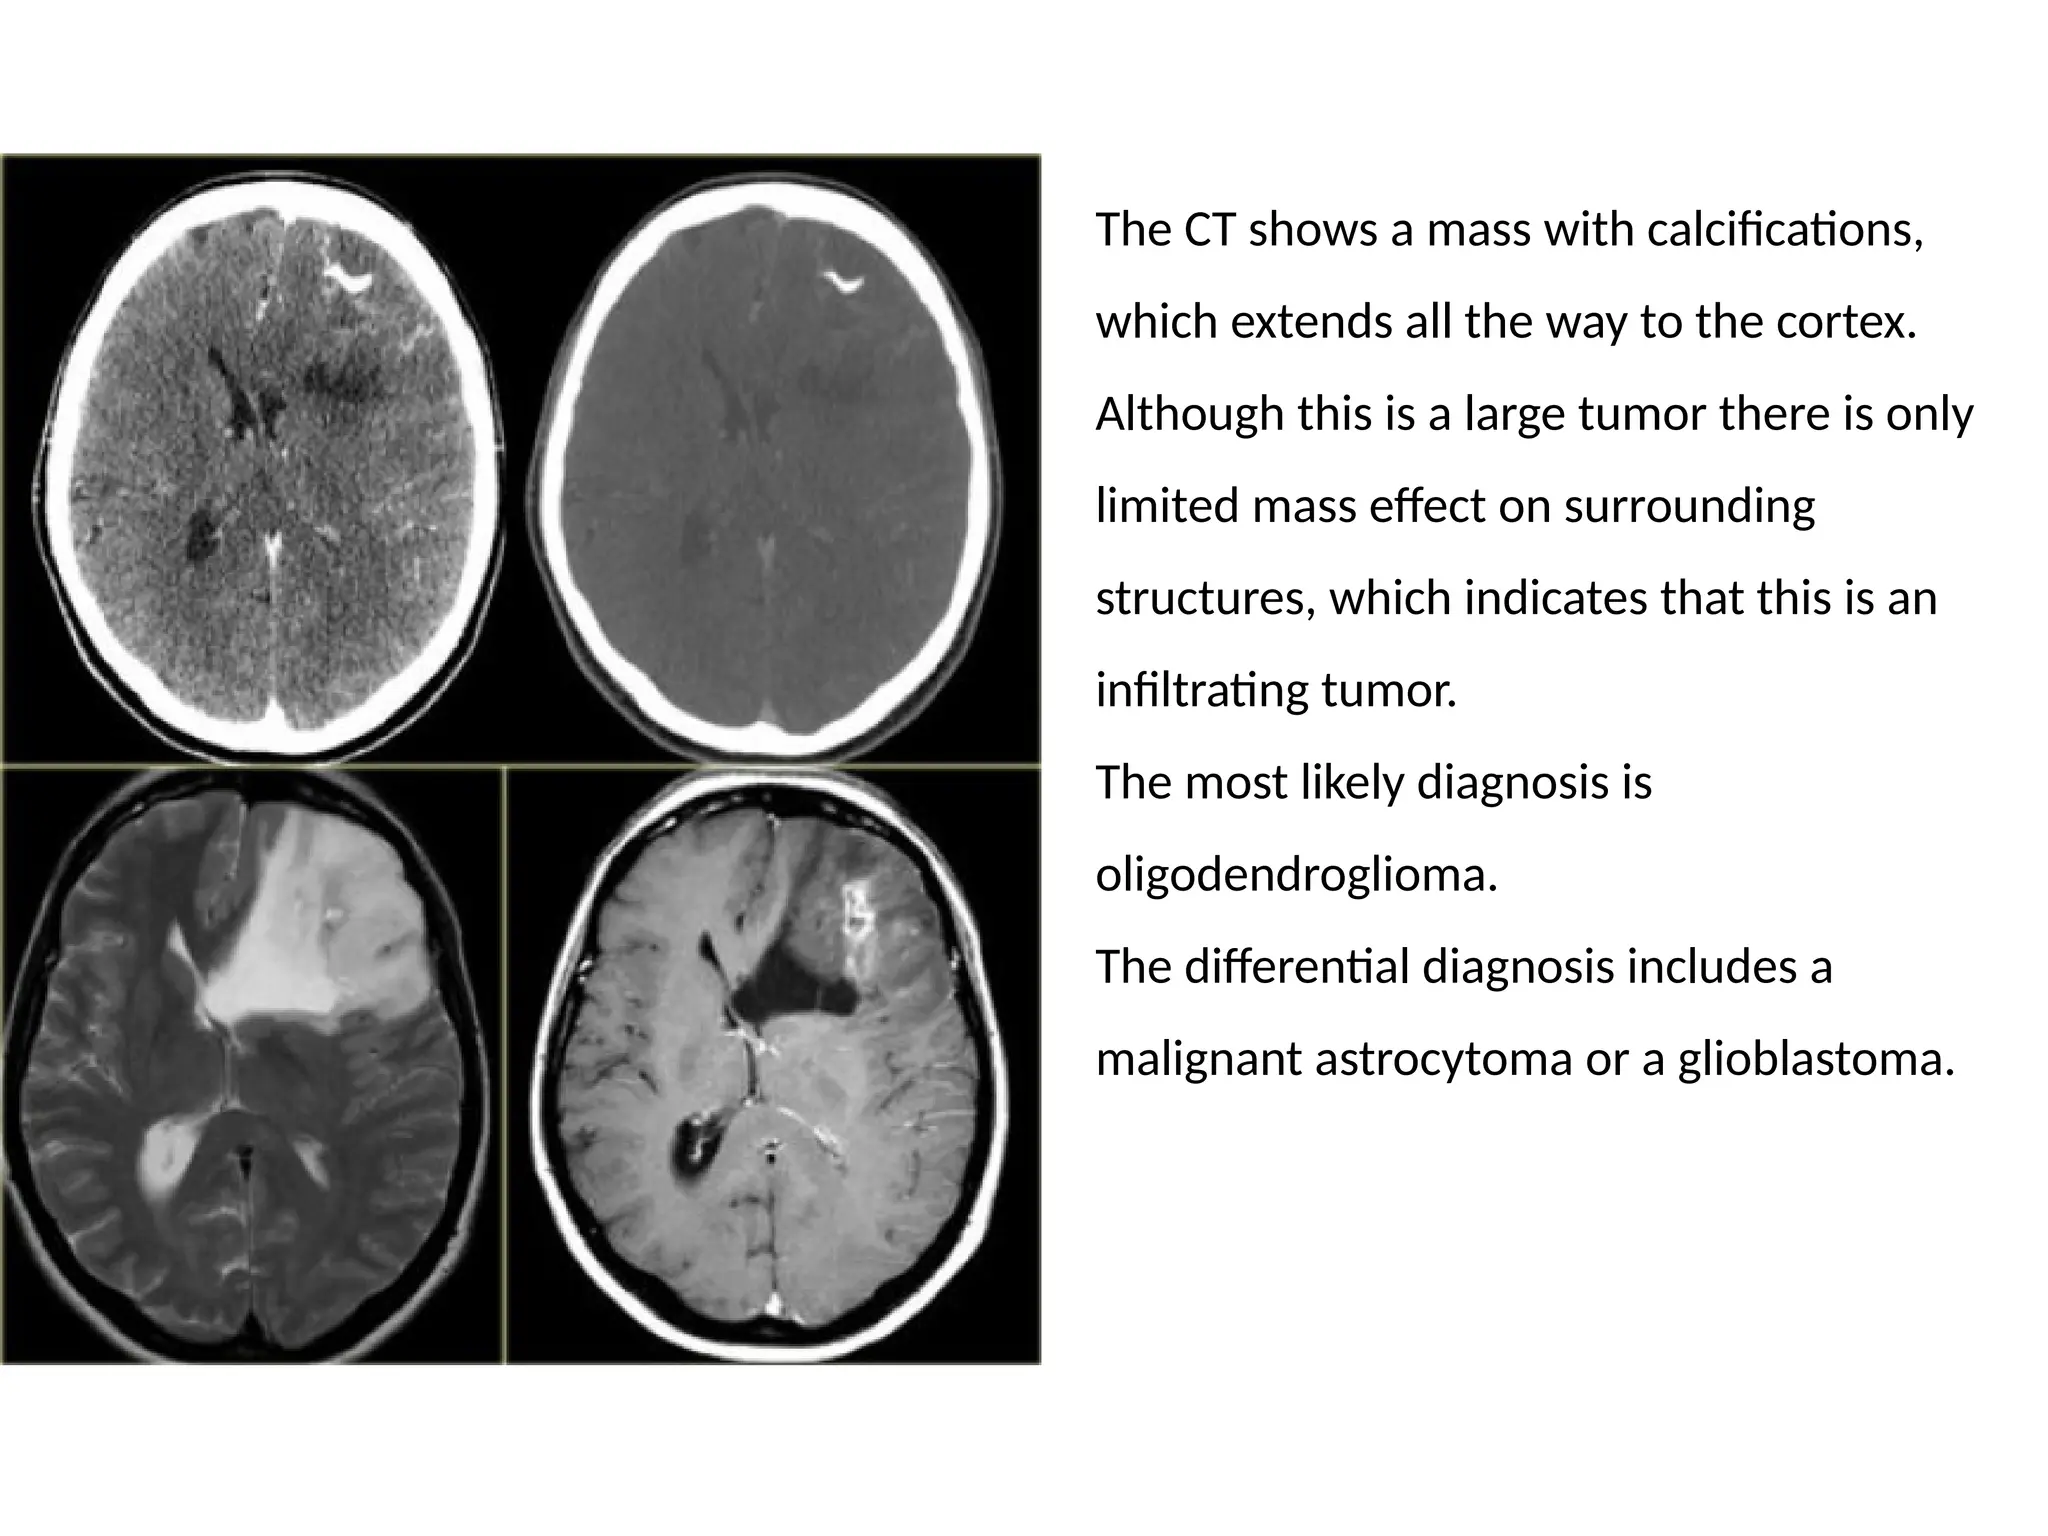

The CT shows a mass with calcifications,

which extends all the way to the cortex.

Although this is a large tumor there is only

limited mass effect on surrounding

structures, which indicates that this is an

infiltrating tumor.

The most likely diagnosis is

oligodendroglioma.

The differential diagnosis includes a

malignant astrocytoma or a glioblastoma.